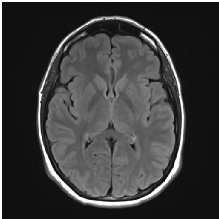

4.3 Dataset description

The objective of our work is to classify MRI images to predict the presence of neoplasms and their severity. In this experiment, an MRI dataset is collected from the online repository of The Whole Brain Atlasjohnson_becker . This website is maintained by Harvard Medical School and has proved to be very authentic in terms of medical imaging datasummers2003harvard . T2 weighted images are used in the experiment as shown in Fig. 9. The types of the MRI for malignant brain neoplasms in the dataset are glioma and sarcoma. And the benign brain neoplasms are metastatic bronchogenic carcinoma(M.B.C.), metastatic adenocarcinoma(M.A.) and meningioma. The shape of an MRI image is h ×\times w ×\times n, where n is the number of slices in each image, h is height and w is width, where h and w both equals to 256.

Refer to caption

Figure 9: Example of stacked brain MRI slices